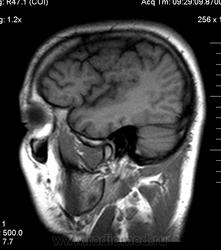

Мужчина 32 лет. Из анамнеза: перинатальное повреждение ЦНС, ДЦП, дизартрия, правосторонний верхний монопарез. С 16 лет приступы эпилепсии.

Аплазия прозрачной перегородки. Шизэнцефалия с открытыми краями в лобно-теменной области слева. Шизэнцефалия с закрытыми краями в лобной области справа? Утолщение коры по контуру расщелин и в области глазничной извилины правой лобной доли. Микрогирия? Гиперостоз костей свода черепа. Уважаемые коллеги, возможно я ошибаюсь, или есть еще аномалия?

На мой взгляд, полимикрогирия двусторонняя (конвекситальные отделы дорзальных отделов лобных долей и частично теменных, а также в базальном отделе полюса правой лобной доли) + закрытая шизенцефалия левой лобно-теменной области. Аплазия прозрачной перегородки (как признаки лобарной голопрозенцефалии).